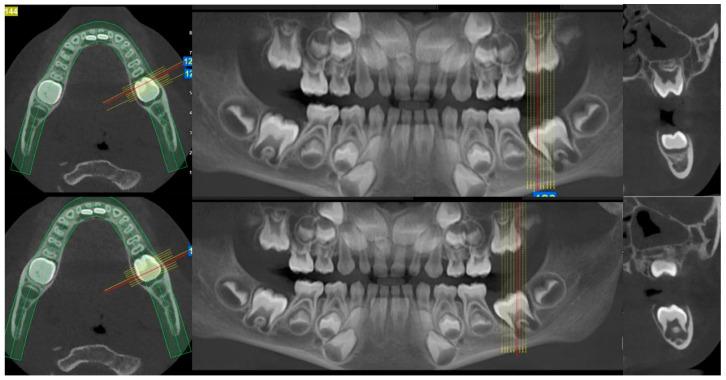

一名6岁男性患者被转诊至希腊塞萨洛尼基亚里士多德大学健康科学学院牙科学院口腔医学/病理学系的研究生诊所,因为他的儿科牙医在常规检查中发现牙齿#75远中处有一个外生性口腔内肿块。首次组织病理学检查显示为牙龈肿瘤,归类为小圆蓝细胞瘤,与釉质瘤样尤因肉瘤(ALES)更为相似,与滑膜肉瘤的相似性较小。第二位病理学家检查了相同的组织标本,并提示极罕见地存在未成熟恶性畸胎瘤。化疗后,切除了畸胎瘤剩余部分及相邻的牙齿#75,组织病理学检查显示为成熟畸胎瘤。